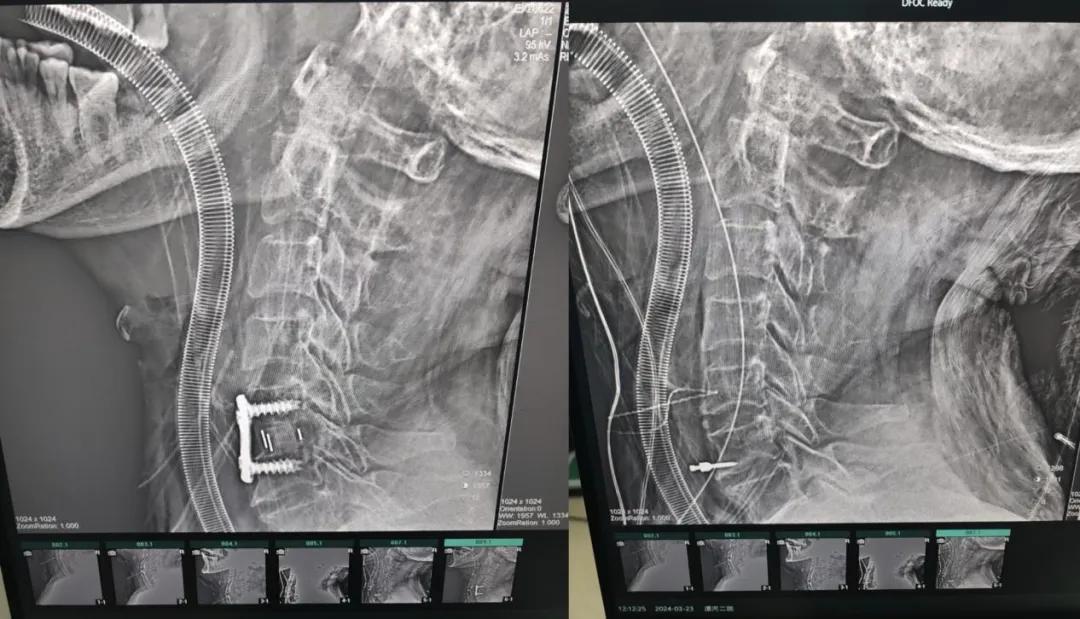

近日,70歲的馬阿姨,因摔傷后出現(xiàn)持續(xù)性頸部疼痛伴右側(cè)肢體無力、麻痛,影響日常生活。于是來到市二院神經(jīng)外科就診,經(jīng)檢查發(fā)現(xiàn):頸椎MR示:頸3/4、4/5、5/6、6/7椎間盤變性突出(中央型)并繼發(fā)性椎管變窄,頸椎退行性改變,頸5椎體水平頸髓水腫。神經(jīng)外科副主任劉沛濤根據(jù)患者癥狀、體征、影像學(xué)三者結(jié)合診斷為“脊髓型頸椎病”,考慮到患者癥狀逐漸加重、保守治療效果不佳等情況,建議盡快手術(shù)治療。

經(jīng)過縝密的術(shù)前準(zhǔn)備和手術(shù)計劃,在鄭大一附院神經(jīng)外科張風(fēng)江教授的指導(dǎo)下,神經(jīng)外科團(tuán)隊(duì)順利為患者實(shí)施“顯微鏡下頸椎前路C5/C6椎間盤切除椎間融合+內(nèi)固定術(shù)”,手術(shù)時間不到1小時。術(shù)后患者恢復(fù)情況良好。